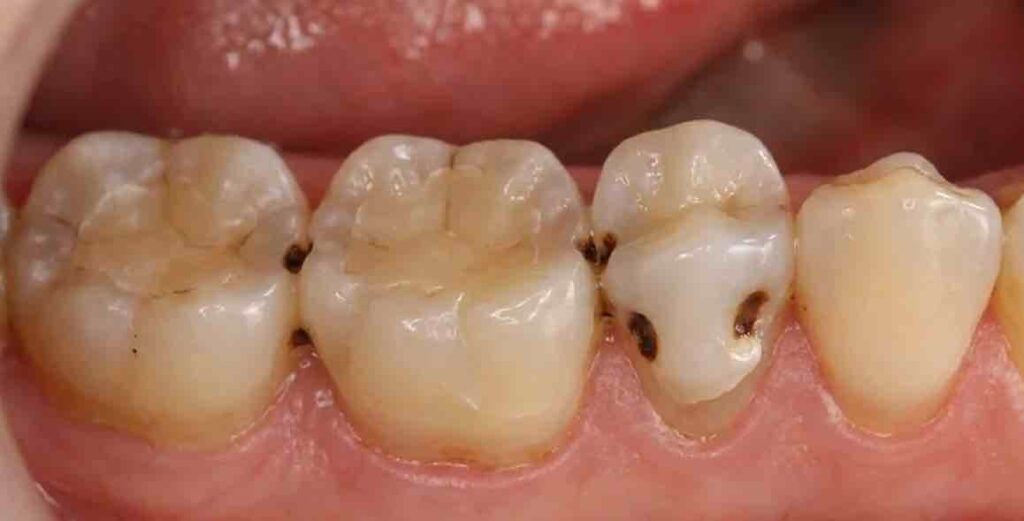

1. 歯と歯の間のむし歯

歯と歯の間にできるむし歯は見えにくいため、気づかないうちに進行しやすい部位です。むし歯が進むと歯が溶けて本来のカーブが失われ、そこに“凹み”ができます。

この凹みが食べ物を受け止める形になってしまい、かむたびに食べ物が入り込みます。